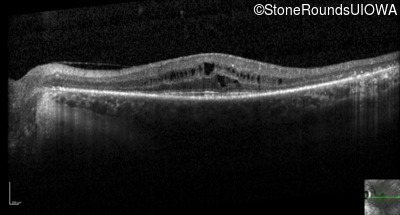

Optical Coherence Tomography - Right - 20/20 -2

Exemplar / OCT Stack

OCT Stack